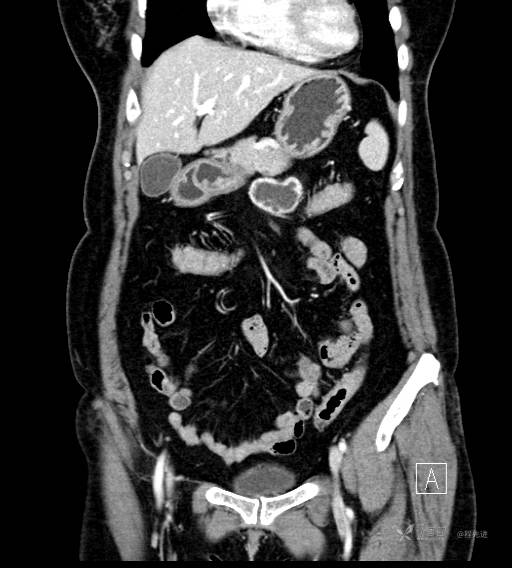

CT增强门脉期